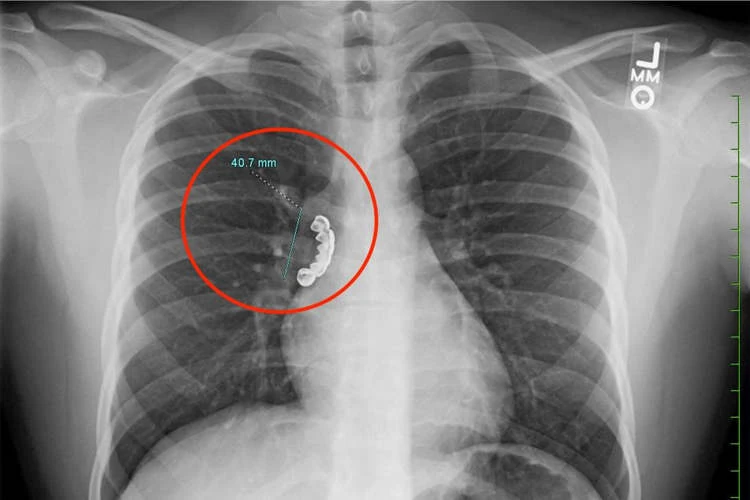

A 22-year-old man put himself in risk in order to have gorgeous teeth when one of the grillz he was wearing came loose, made its way into his lungs, and became lodged there.

Unknown man sought medical attention, and after having X-rays taken of him, physicians discovered that he had a 4-cm-long object that resembled dentures caught in the right main stem bronchus, the lung’s airway.